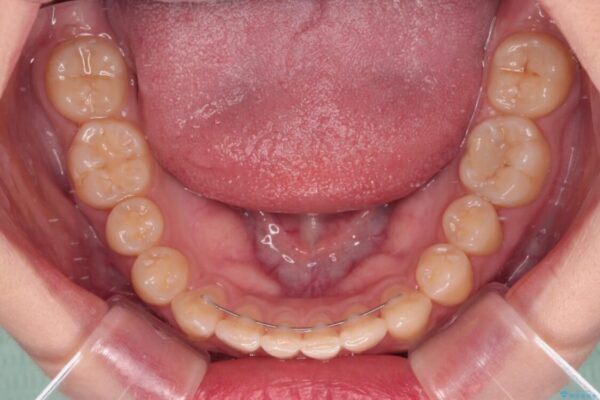

根管治療を行ったままの奥歯と、矯正治療の後戻りを気にして来院された患者様です。

矯正治療の後戻りは軽微であったため、インビザラインの簡易パッケージであるインビザライン・ライトを用いて歯列を整えることとしました。

治療前

• 治療途中の奥歯と矯正治療の後戻り インビザライン・ライトによる矯正治療 治療前画像